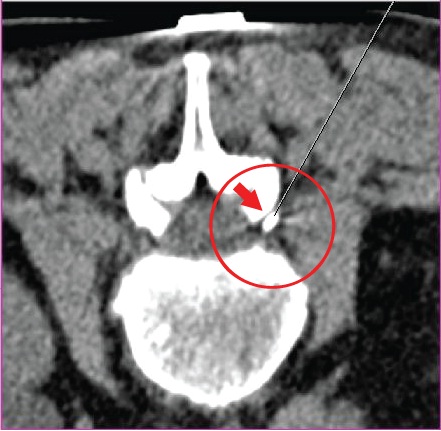

![]() КТ пояснично-крестцового позвоночника. рентгенография пояснично |

КТ пояснично-крестцового отдела позвоночника после лечения.